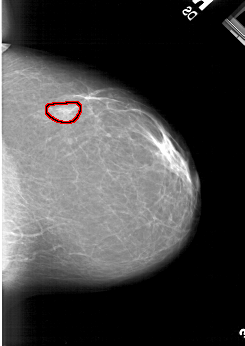

A_1177_1.LEFT_CC

LEFT_CC LINES 6151 PIXELS_PER_LINE 4261 BITS_PER_PIXEL 12 RESOLUTION 43.5 NON_OVERLAY

FILE: A_1177_1.RIGHT_CC.OVERLAY

TOTAL_ABNORMALITIES 1

ABNORMALITY 1

LESION_TYPE MASS SHAPE LOBULATED MARGINS OBSCURED

ASSESSMENT 3

SUBTLETY 4

PATHOLOGY BENIGN

TOTAL_OUTLINES 1

BOUNDARY